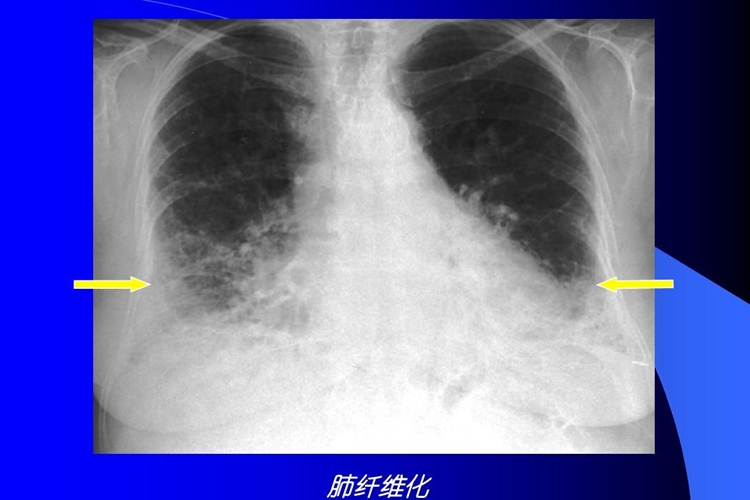

正常肺组织和肺部纤维化的区别通过影像学检查可明确,正常肺部结构的轮廓清晰,无扭曲变形,而肺部纤维化可见网格状阴影和蜂窝影。

肺部纤维化的影像学特征为胸膜下或肺基底部的网格状阴影和蜂窝影,常伴有牵张性支气管扩张。高分辨率CT上的蜂窝影指成簇的囊泡样气腔,蜂窝壁边界清楚。囊泡直径在一般为3-10mm,偶尔可大至25 mm。磨玻璃影常见,但其范围少于网格状影。